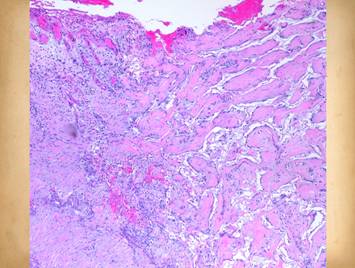

Left, a microscope image of normal wound healing.  The structure shown here is the prototypical wound.  Details of the structure and process will be explained in following panels.  Right, the microscopic appearance of fully regenerated Integra-CG matrix, the details likewise to be explained in following panels.  Even without explaining or focusing on specific details, the dissimilarity of the two can be appreciated.  Angiocytes and fibroblasts, vessels and connectives – that is all there is to these two tissues.  However, by supplying different “rules” or “subroutines” for the interaction and assembly of these elements, two different biomaterials emerge.  The rules or routines are based on the circumstances, reaction-to-injury versus embryonic regeneration.  The results have very different physical properties and implications for daily life, functional adaptations, and potential need for ongoing medical care.

Pictured is matrix regeneration within a piece of Integra collagen-gag matrix.  It is no longer the non-living empty matrix placed on the original wound, but a fully restored living material.  The details of this process are now presented.  However, even without knowing the specific details, it can be appreciated that the structure, morphology, and patterns of this regenerated biological material are different than the microscopic structure of the normal post-inflammatory wound.  Normal wound healing is triggered by inflammation and then evolves according to its own “program” of how angiocytes and fibroblasts rebuild a stroma of blood vessels and connective mesh.  Integra suppresses inflammation, and thus the normal “wound healing program” is never turned on.  Integra “heals” by a fundamentally different mechanism analogous to embryonic tissue generation.  Its build to a state of complete regeneration is uniform throughout the matrix, distributed rather than stratified, and when complete, it has created a new material that has characteristics mostly like normal dermis and quite unlike scar.  The matrix coaxes the same two cells, angiocytes and fibroblasts, to make a new tissue of blood vessels and connective mesh in a patterned morphology that is profoundly different then scar.  The same cells, making the same elemental components, assemble them in a completely different pattern than wound healing and scar because the embryogenesis-and-stromal-generation “program” is entirely different than the healing-and-scar “program”.